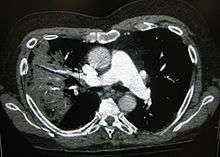

A chest radiograph is frequently used in diagnosis.[19] In people with mild disease, imaging is needed only in those with potential complications, those not having improved with treatment, or those in which the cause is uncertain.[19][48] If a person is sufficiently sick to require hospitalization, a chest radiograph is recommended.[48] Findings do not always match the severity of disease and do not reliably separate between bacterial infection and viral infection.[19]

X-ray presentations of pneumonia may be classified as lobar pneumonia, bronchopneumonia (also known as lobular pneumonia), and interstitial pneumonia.[51] Bacterial, community-acquired pneumonia classically show lung consolidation of one lung segmental lobe, which is known as lobar pneumonia.[29] However, findings may vary, and other patterns are common in other types of pneumonia.[29] Aspiration pneumonia may present with bilateral opacities primarily in the bases of the lungs and on the right side.[29] Radiographs of viral pneumonia may appear normal, appear hyper-inflated, have bilateral patchy areas, or present similar to bacterial pneumonia with lobar consolidation.[29] Radiologic findings may not be present in the early stages of the disease, especially in the presence of dehydration, or may be difficult to be interpreted in the obese or those with a history of lung disease.[20] A CT scan can give additional information in indeterminate cases.[29]

In rare circumstances, bacteria in the lung will form a pocket of infected fluid called a lung abscess.[90] Lung abscesses can usually be seen with a chest X-ray but frequently require a chest CT scan to confirm the diagnosis.[90] Abscesses typically occur in aspiration pneumonia, and often contain several types of bacteria. Long-term antibiotics are usually adequate to treat a lung abscess, but sometimes the abscess must be drained by a surgeon or radiologist.[90]